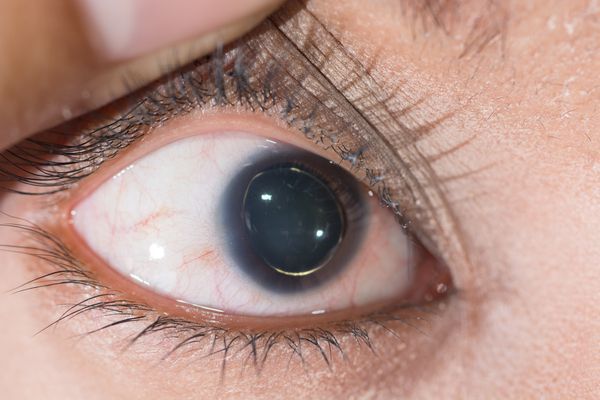

Sindrom marfana tema nauchnoj stati po klinicheskoj medicine chitajte besplatno tekst nauchno issledovatelskoj raboty v elektronnoj biblioteke kiberleninka (Тип файлу jpg)

Sindrom Marfana Tema Nauchnoj Stati Po Klinicheskoj Medicine Chitajte Besplatno Tekst Nauchno Issledovatelskoj Raboty V Elektronnoj Biblioteke Kiberleninka

Neonatalnaya forma sindroma marfana klinicheskoe opisanie i kompleksnyj podhod k diagnostike i lecheniyu tema nauchnoj stati po klinicheskoj medicine chitajte besplatno tekst nauchno issledovatelskoj raboty v elektronnoj biblioteke kiberleninka (Тип файлу jpg)

Neonatalnaya Forma Sindroma Marfana Klinicheskoe Opisanie I Kompleksnyj Podhod K Diagnostike I Lecheniyu Tema Nauchnoj Stati Po Klinicheskoj Medicine Chitajte Besplatno Tekst Nauchno Issledovatelskoj Raboty V Elektronnoj Biblioteke Kiberleninka

Neonatalnaya forma sindroma marfana klinicheskoe opisanie i kompleksnyj podhod k diagnostike i lecheniyu tema nauchnoj stati po klinicheskoj medicine chitajte besplatno tekst nauchno issledovatelskoj raboty v elektronnoj biblioteke kiberleninka (Тип файлу jpg)

Neonatalnaya Forma Sindroma Marfana Klinicheskoe Opisanie I Kompleksnyj Podhod K Diagnostike I Lecheniyu Tema Nauchnoj Stati Po Klinicheskoj Medicine Chitajte Besplatno Tekst Nauchno Issledovatelskoj Raboty V Elektronnoj Biblioteke Kiberleninka

Sindrom marfana tema nauchnoj stati po klinicheskoj medicine chitajte besplatno tekst nauchno issledovatelskoj raboty v elektronnoj biblioteke kiberleninka (Тип файлу jpg)

Sindrom Marfana Tema Nauchnoj Stati Po Klinicheskoj Medicine Chitajte Besplatno Tekst Nauchno Issledovatelskoj Raboty V Elektronnoj Biblioteke Kiberleninka